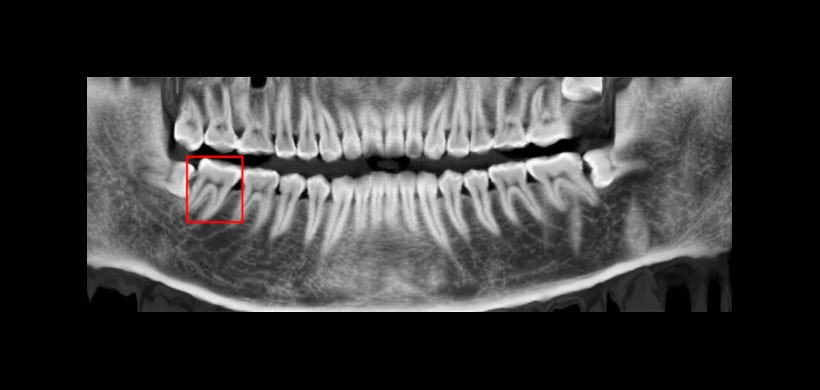

En este estudio se utilizaron conjuntos de datos CBCT en forma de mordida, las imágenes resultantes se analizaron para evaluar la eficacia de este método. Con el cual, una reformación panorámica de una sola pieza puede mostrar la dentición completa sin el desenfoque y superposición de otras estructuras. Además, También se pueden sintetizar reformaciones panorámicas con diferentes tipos de grosores. Mostrando otras características como el canal nervioso mandibular. (Figura 2)

Figura 2: Reformación panorámica